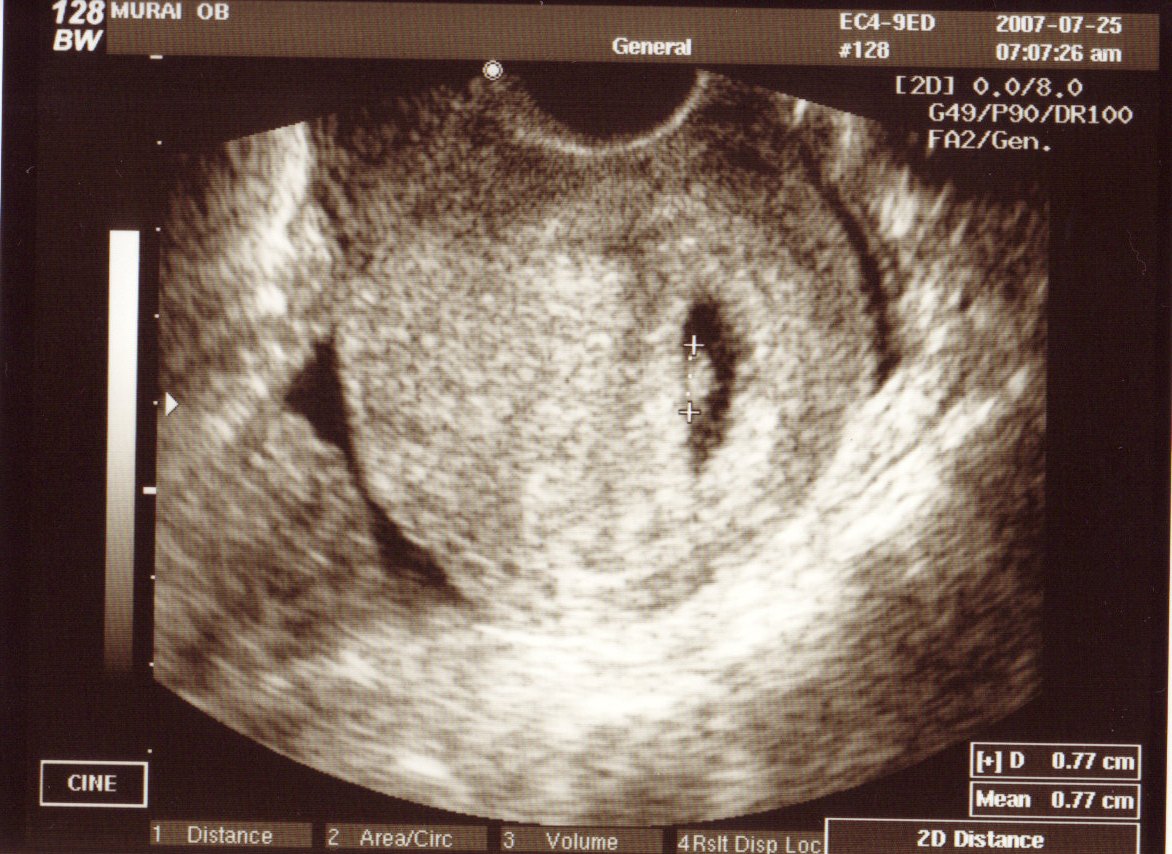

まだ8週目なのに、今回は腹部エコー

しかも、その様子をDVDに録画してくれていて、いただいて帰りました。